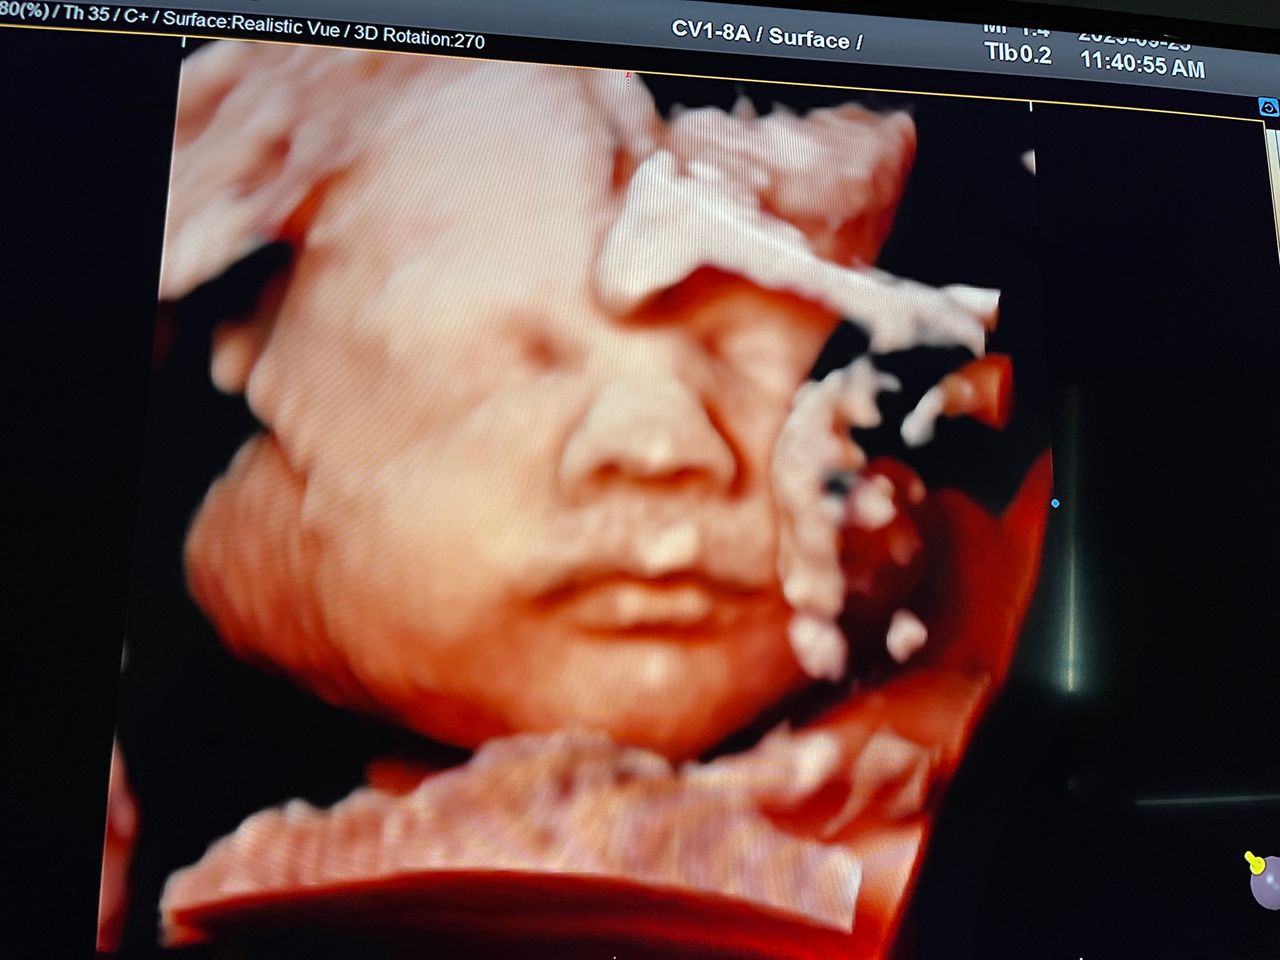

Attualmente lavoro come Dirigente medico nella SC di Ostetricia e Ginecologia dell'Ospedale Michele e Pietro Ferrero di Verduno, mi occupo prevalentemente di screening prenatale, ecografia ostetrica del I trimestre( misurazione translucenza nucale,NT), ecografia morfologica del II trimestre, ambulatorio pregresso taglio cesareo, ecografia ostetrica 3D. Seguo le gravidanze fisiologiche e quelle ad alto rischio , presto servizio in sala parto. Eseguo visite ginecologiche di I-II livello in regime ambulatoriale, counseling contraccettivo ed eventuale prescrizione pillola, inserimento spirale (IUD), dispositivo sottocutaneo (Nexplanon).

Foto e video